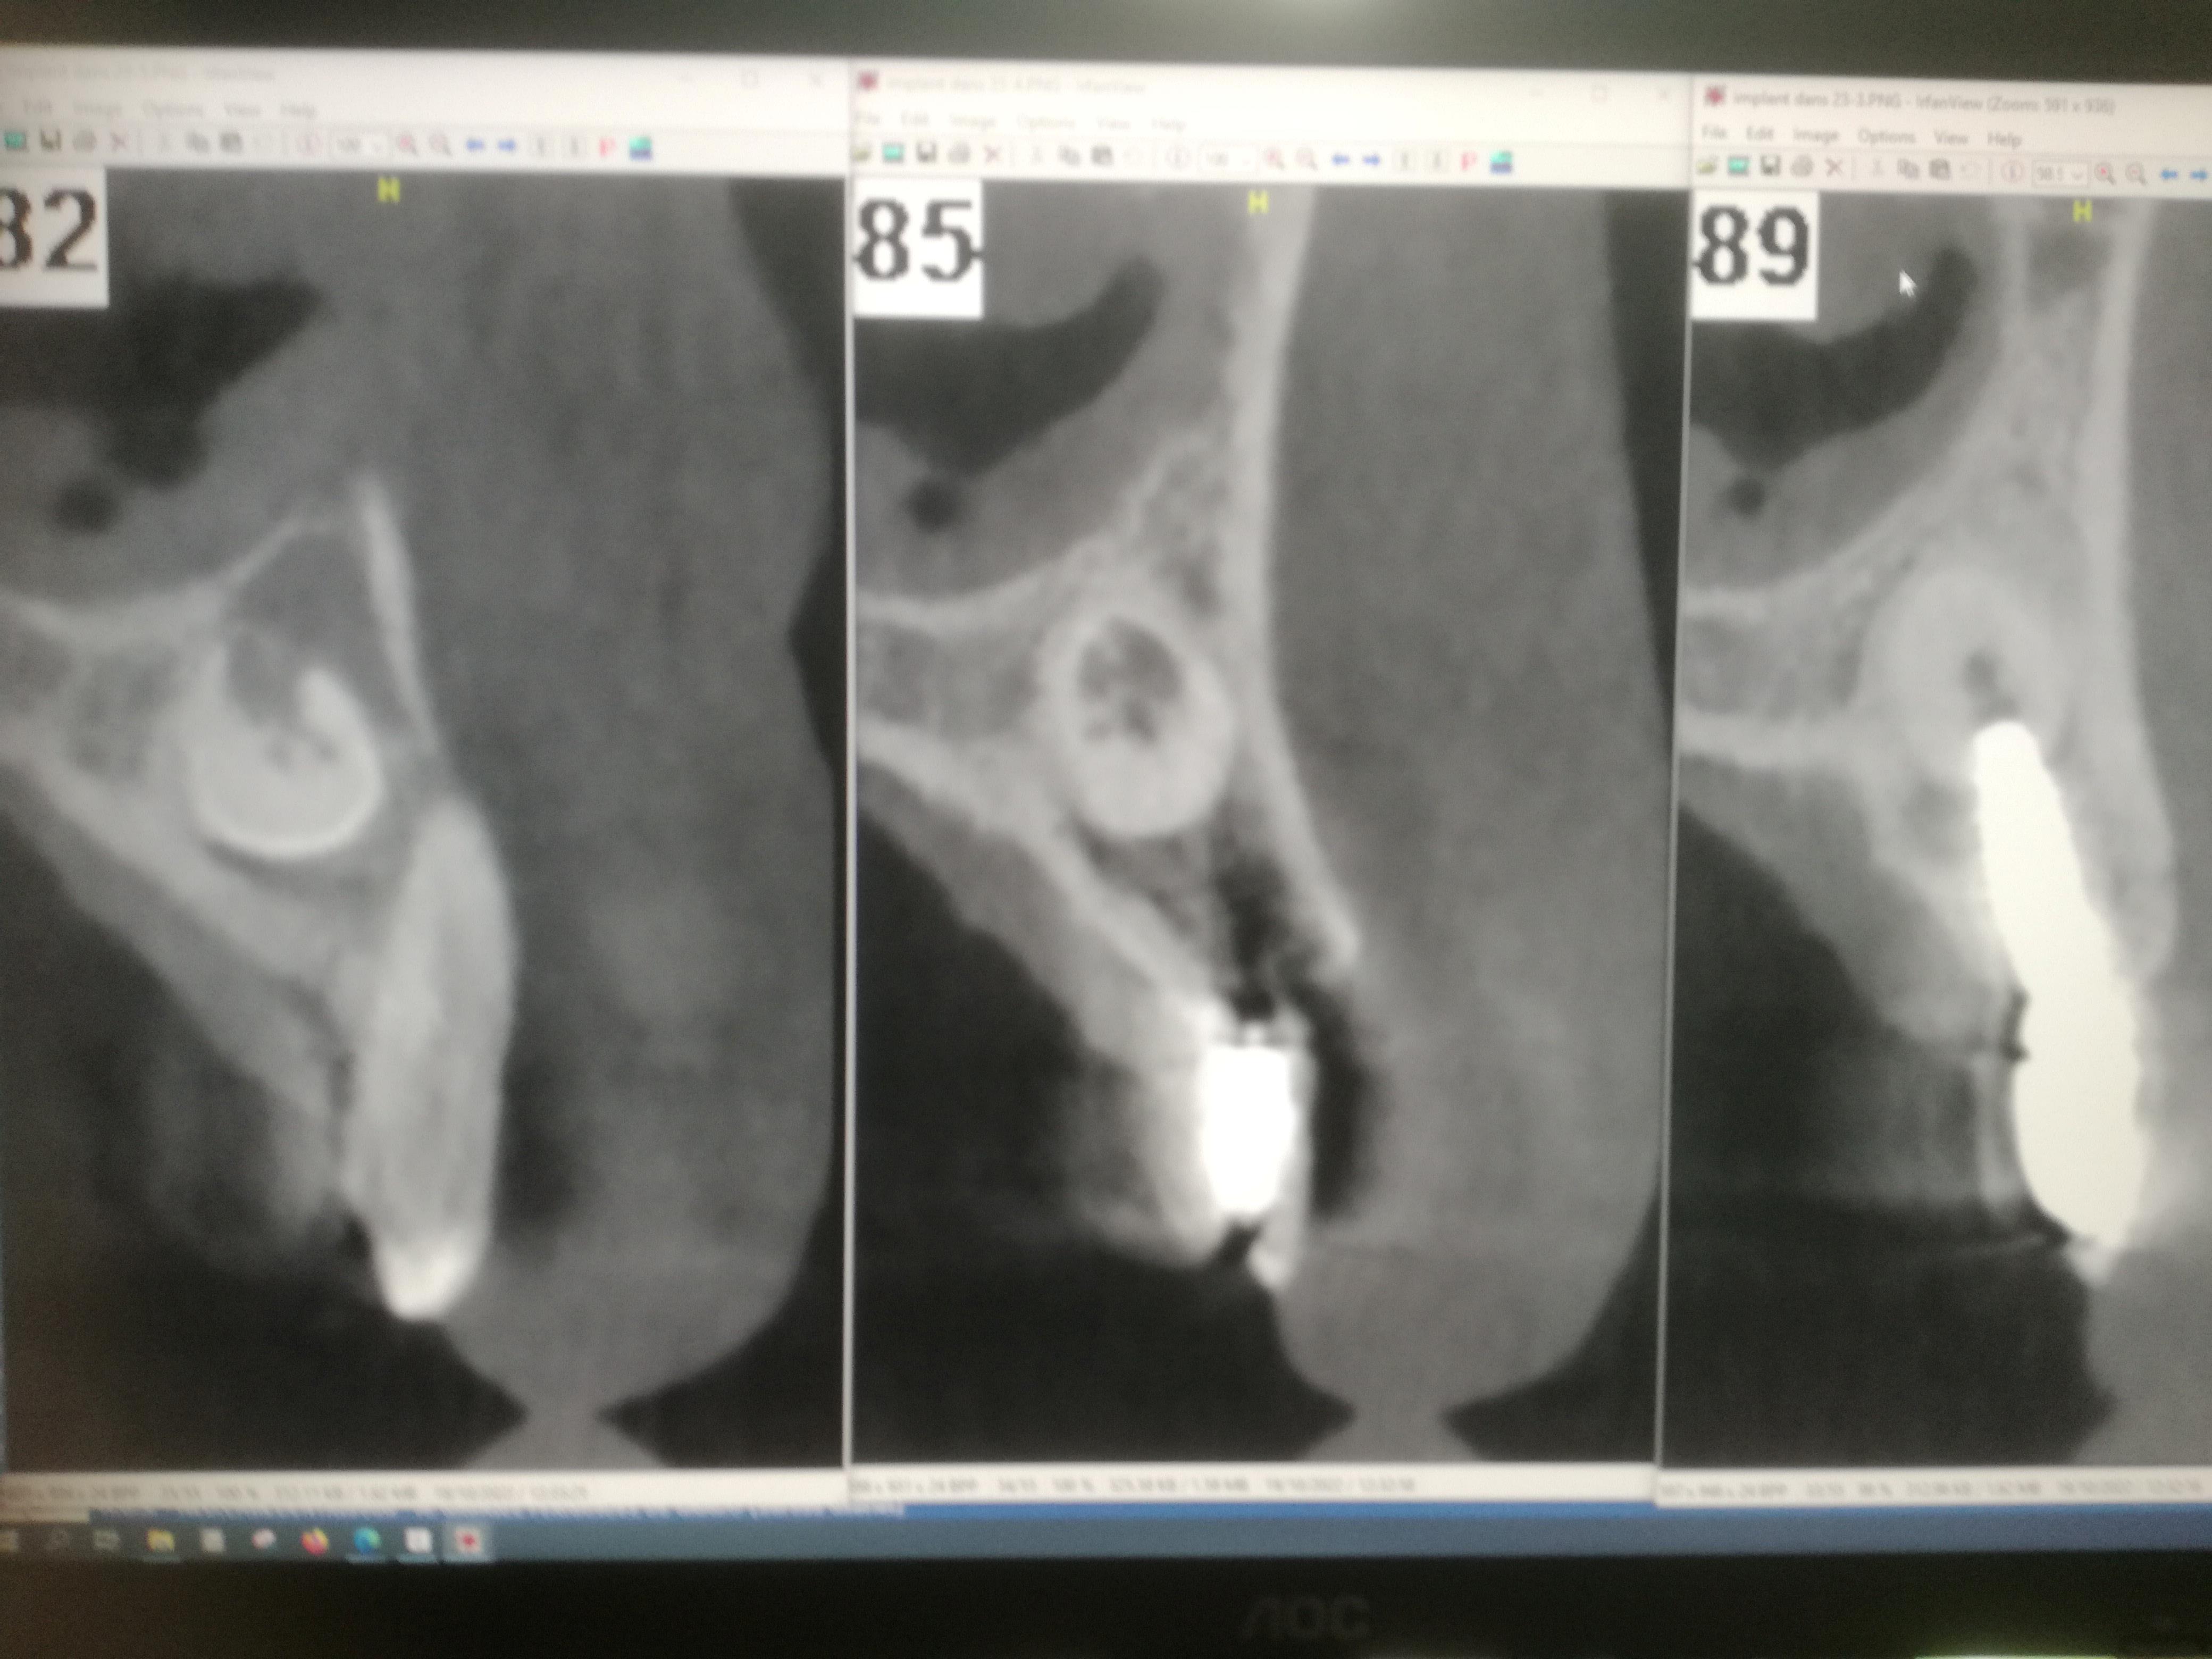

Que pensez vous de cette canine incluse? J'hésite à me lancer pour l'extraire avant d'implanter ou alors de la transfixer comme le fait Davarpannah.

Ca je vire avant de poser mon implant !

Proprement histoire de bien garder l’os au dessus et en dessous.

Puis implant super long pour bien le stabiliser. Si c’est le cas, une mise en esthétique immédiate et un peu de bio-oss dans l’alvéole ( ça c’est plus une croyance après avoir eu une galère sans en mettre. Pas sûr que ce soit indispensable mais dans le doute je mets)

surtout qu'à vue de nez, c'est ce qui a été fait de l'autre côté donc pourquoi chercher les emmerdes?

Dans le cas que tu as montré Gabzou le praticien a fait une effraction pulpaire…. Je te fais un petit zoom.

Dans ton cas Palpatine, je dis qu’il y a moyen de le faire sans effraction pulpaire. Foret initial et expansion (donc sans rogner d’avantage la dentine).

Ici l’axe de l’implant ne tombe absolument pas dans le nerf de la dent . Et il y aura une osteo intégration de l’implant sur le 1/3 sup , sur le 1/3 inf , et en vestibulaire quasi tout le long .